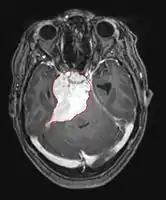

• CT

• Well-defined extra-axial mass that displaces normal brain. Smooth in contour, sometimes calcified

• About 60% hyperdense with normal brain without contrast

• About 70% brightly and homogenously enhance with contrast (less frequent in malignant or cystic meningiomas)

• MRI

• Preferred imaging because it can show dural origin

• Dural tail sign seen in about two-thirds: characteristic marginal thickening that tapers peripherally along the dura

• Isointense on T1, hyperintense (usually homogeneously) on T2, strong enhancement with IV contrast